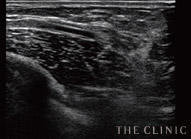

しこりの状態

しこりの大きさを把握することも重要ですが、ヒアルロン酸がどうなっているかで対処法が違ってきます。炎症や瘢痕化を起こしていないかなどもエコー検査から読み取ります。

しこりの状態で処置を判断

ヒアルロン酸豊胸のしこりの除去方法は、しこりの状態によって異なります。通常なら、ヒアルロン酸溶解液のヒアルロンダーゼを注射することで、解決できます。瘢痕化したしこりは切開する必要がありますが、多くのケースはバストにメスを入れなくても、しこりの除去が可能です。

また、ヒアルロン酸の注入時期やしこりの大きさによっては、自然に吸収されて消失することも。そういった診断も含めて、対処法をご提案します。